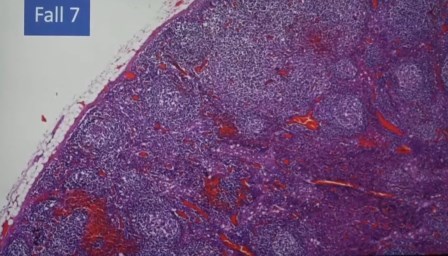

Nodo linfático de casi cuatro centímetros, fuerte reacción inmune, linfoma

Los folículos del nódulo linfático